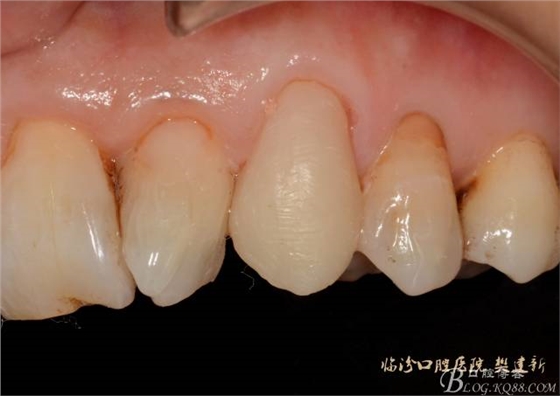

圖10修復(fù)體代入口內(nèi)照

圖12修復(fù)體代入口內(nèi)正面照